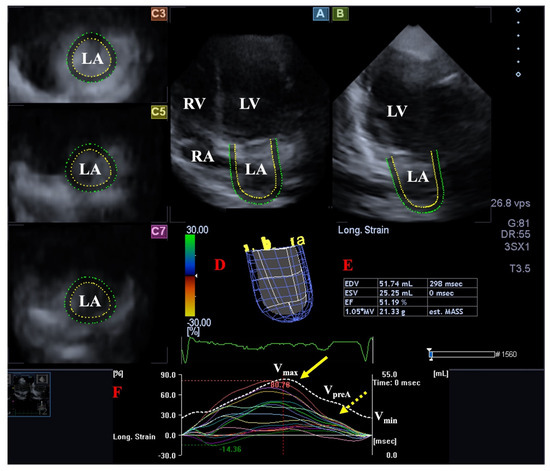

Long-Term Follow-Up of Professional Soccer Players: The Analyses of Left and Right Heart Morphology and Function by Conventional, Three-Dimensional, and Deformation Analyses

Background: Transthoracic echocardiography (TTE) is the primary imaging modality to assess cardiac morphology and function. In athletes, distinguishing physiological adaptations from pathological changes is essential. This study aimed to evaluate long-term cardiac structural and functional changes in professional soccer players. Methods: This retrospective [...] Read more.

Background: Transthoracic echocardiography (TTE) is the primary imaging modality to assess cardiac morphology and function. In athletes, distinguishing physiological adaptations from pathological changes is essential. This study aimed to evaluate long-term cardiac structural and functional changes in professional soccer players. Methods: This retrospective study included 20 healthy male professional soccer players (mean age 21.2 ± 3.4 years) from the German first division, examined annually from 2016 to 2024 (mean follow-up 5.6 ± 2.0 years). TTE parameters associated with the “athlete’s heart” were assessed, including left ventricular end-diastolic diameter (LVEDD), interventricular septal thickness (IVSD), relative wall thickness (RWT), indexed LV mass (LVMi), and left atrial volume index (LAVi), along with 3D-derived LV and RV volumes. Advanced deformation imaging included global longitudinal strain (GLS), right ventricular strain (RVS), and left/right atrial reservoir strain (LASr and RASr, respectively). Baseline and final follow-up values were compared. Results: No significant changes were observed over time in conventional or advanced echocardiographic parameters (e.g., LVEDD: 54.5 ± 3.1 mm vs. 54.6 ± 3.9 mm; p = 0.868; GLS: −18.7% ± 2.2% vs. −18.4% ± 1.9%; p = 0.670). Ventricular volumes and strain values also remained stable throughout follow-up. Conclusions: Over a mean follow-up of more than five years, professional soccer players showed stable cardiac morphology and function without evidence of pathological remodeling. These findings support the concept that long-term high-level training in mixed-discipline sports leads to balanced, physiological cardiac adaptation. Full article